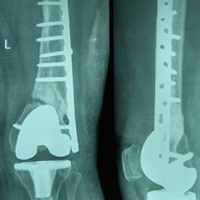

Case:14 Periprosthetic Fracture

60 years old patient with total knee replacement on left knee presented with open grade 1 injury. Debridement & slab given on emergency bases. Fixation with plate & screws done. Union was seen after 6 months.

Pre-Op AP

Pre-Op Lat.

Immdiate Post-op

1 and half months Post-op

2 and half months Post-op

3 and half months Post-op

4 and half months Lateral

6 Years Follow-Up